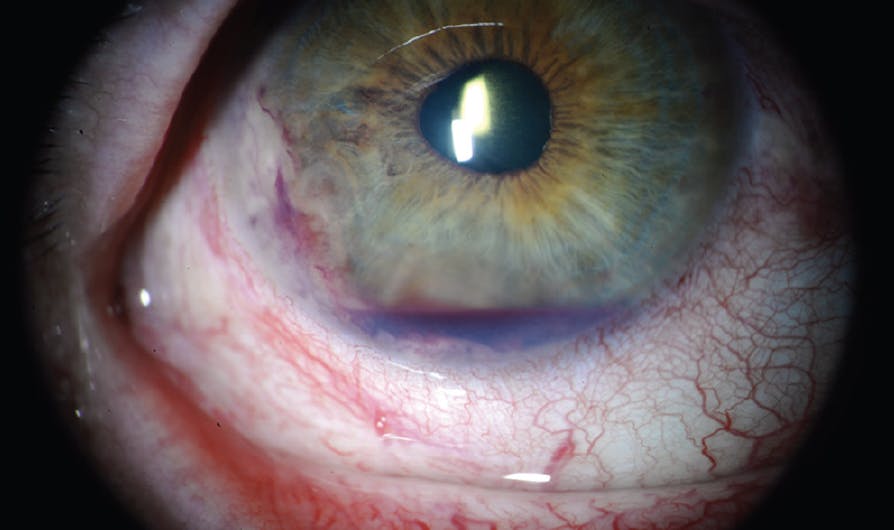

At the initial examination, his BCVA was 20/70 OD and 20/40 OS. IOP was 23 mm Hg OD and 17 mm Hg OS. The anterior segment of the right eye revealed moderate conjunctival and scleral injection with 20% hyphema overlying a milky-white, fluffy-appearing solid vascularized mass involving 6 clock hours of the iris and angle inferiorly (Figure 1). Anterior segment OCT documented the mass in the angle with endothelial touch (Figure 2).

Figure 1. Slit-lamp examination of the right eye documented hyphema, corectopia, and a solid vascularized mass in the inferotemporal angle.